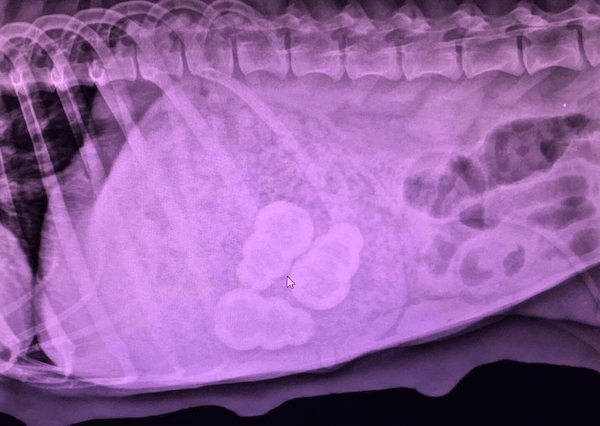

When choosing an interactive dog feeder, make sure it is the correct size for your dog. It should be too large to swallow. You don't want your dog choking or swallowing their stuffable toy. There are quite a few stories of dogs swallowing KONGs whole. In the X-ray below, a mother dog ingested the small-sized KONGs that were meant for her puppies to enjoy.